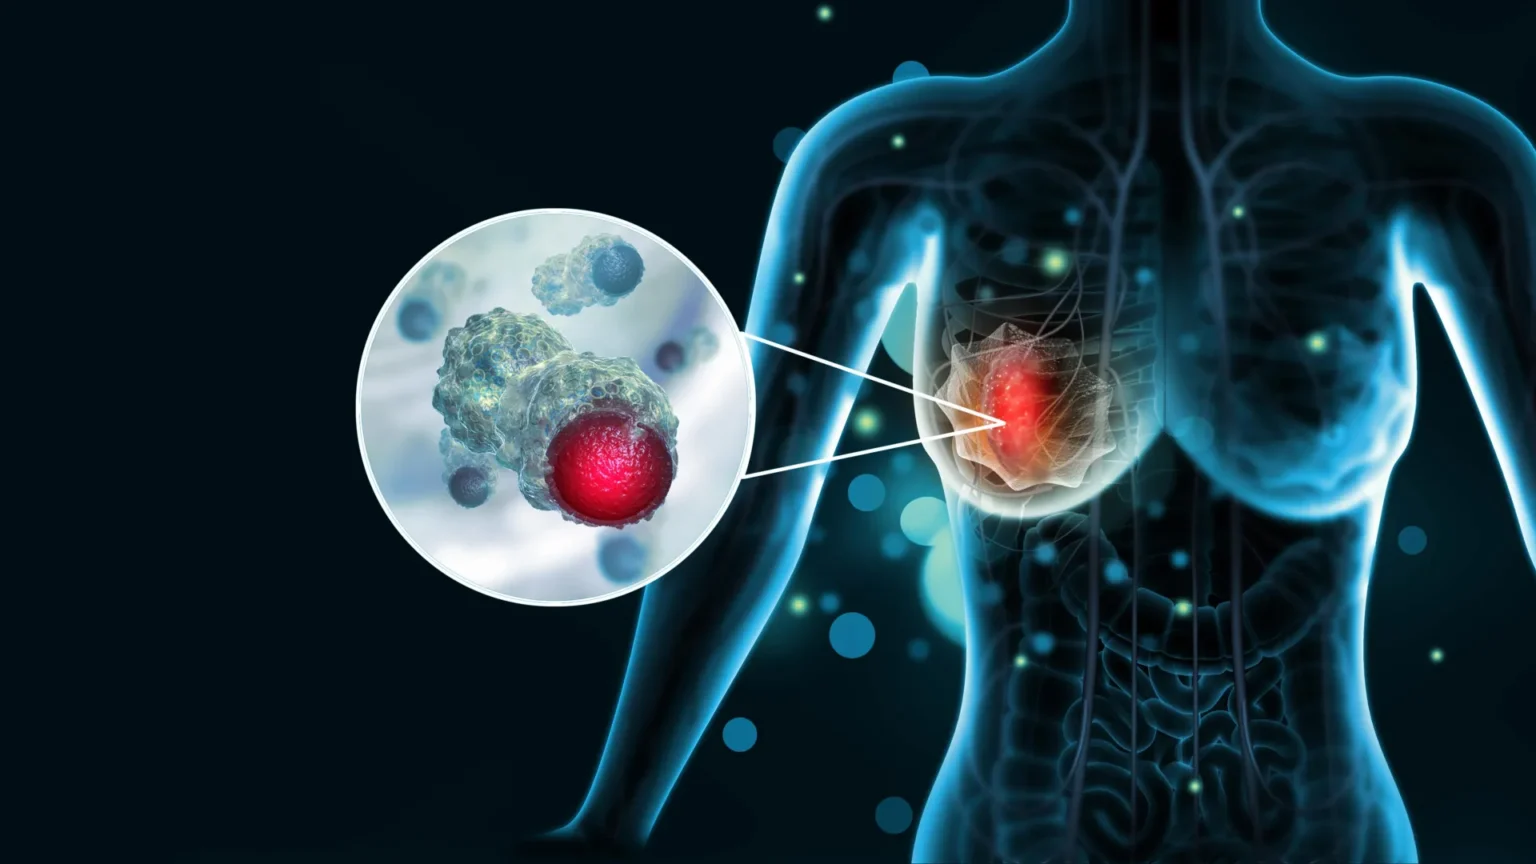

Breast cancer is the most commonly diagnosed cancer in women worldwide. According to the World Health Organization, about 2.3 million women will be diagnosed with the disease in 2022, and about 670,000 will die from the disease. Although treatments have improved in recent years, some forms of breast cancer are particularly aggressive and difficult to manage. One of the biggest challenges doctors face is that there is no reliable way to predict how these rapidly growing cancers will progress.

These clues, known as biomarkers (measurable biological signals in blood, tissue, and other samples), help doctors monitor how cancer progresses over time and decide on treatments. For example, certain biomarkers may indicate whether a tumor is likely to grow rapidly or respond to certain treatments.

This environment includes not only cancer cells but also nearby immune cells, blood vessels, and other supporting structures. The research team is particularly interested in small molecules found on the surface of cells in this environment. These molecules may play an important role in helping tumors evade detection by the immune system, effectively allowing cancer to grow unchecked.